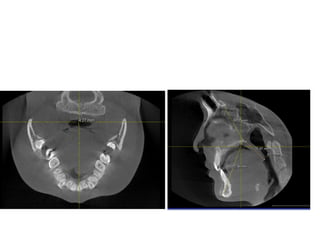

790516

810410

蕭郁庭